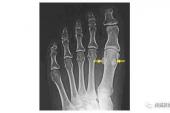

- 1, 目的探讨撕脱性骨折与永存性骨骺、籽骨、副骨的影像学鉴别办法.2, 目的探讨籽骨软骨软化症的病因、病理。3, 经临床和解剖学研究证实,籽骨与狭窄性腱鞘炎的形成有密切的关系,籽骨一定程度上可以导致